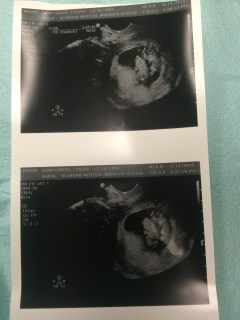

I’ve decided to post my old blog’s pregnancy update posts on this blog as a series… I will repost them here, word for word from my personal blog, “Life with the Febbos.” I hope re-visiting my last years life will help me in healing and maybe let those of you who didn’t know every bit of my pregnancy’s progress understand a little more what i am currently going through. This first one, “The News” was posted on March 28th of last year to my personal blog a couple weeks after finding out I was carrying twins. It’s so fun to remember my excitement and astonishment upon seeing those two little peanuts for the very first time.

—“First Ultrasound;”

“Just a few days ago (well 14 days now,) Warren and I got a big surprise. Two weeks ago, Monday, at my first ultrasound, the 14th of March, we learned that we are expecting twins. Two little figures showed white against the darkness, and two little heartbeats were heard. Warren was the first to detect the presence of more than one, and was afraid to speak out for fear he was right. When he did ask the midwife, “Only one?” she moved around and realized there were two of them! We had to wait in the ultrasound room for an hour then until an ultrasound tech specialist could come measure their progress and give me an updated EDD. When she finally came, we learned the younger of the two was 9weeks and 3 days at the time, and their due date was subject to a few weeks fluctuation. We also learned the type of twins we are expecting and that I would be coming in much more frequently than I’d previously expected to, the first of which being only one week from that day!”

“I had another ultrasound, just one week after that first one. We needed to go in and meet with an OB (since originally I had met with a midwife as that was my preference.) We got lots more pictures of my little ones to look at while we wait for the next visit, (which I will be getting an ultrasound visit every two weeks as my pregnancy is a more ” high-risk”) The news is now almost constantly on the brain, “Twins. I am making twins. There are going to be two babies…” But being sore and nauseous is pretty annoying at this point, so I am counting the days until the glorious SECOND TRIMESTER when they say this can be over!”